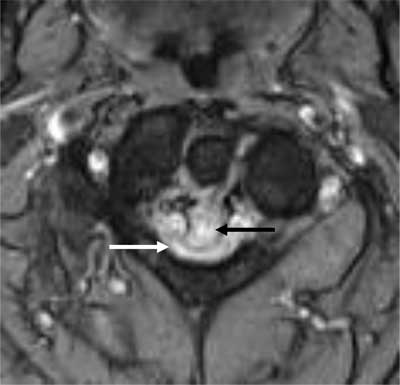

Figure 1

Axial T2-weighted image. The retro-odontoid pseudotumor is seen as a hyperintense mass (black arrow) which extrudes through the transverse ligament and compresses the myelum (white arrow).